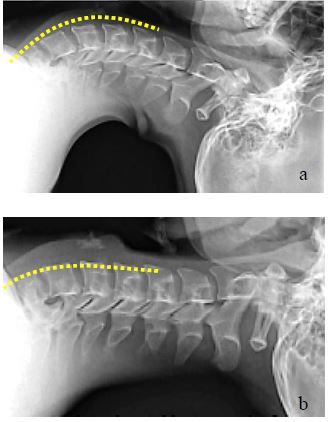

- The proximal oesophagus follows the lordosis of the cervical and thoracic spine; bring the cervical spine into a straight line with the thoracic spine by elevating the head (Figures 27a, b)

- Prominent osteophytes may impair advancement of the scope and make traumatising the mucosa more likely (Figure 28)